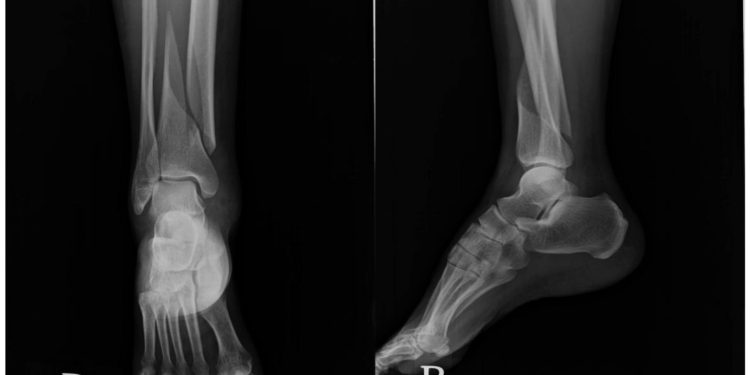

اندام آسیب دیده توسط جراح پا یا دکتر شکستگی مچ پا معاینه شده و برای ارزیابی آسیب، نواحی خاصی لمس مشود. علاوهبراین، در صورت لزوم، جراح ممکن است عکسبرداری با اشعه ایکس و سایر تصویربرداریهای تشخیصی را تجویز کند.

درمان های شکستگی مچ پا

معمولاً برای بررسی اینکه آیا مچ پای شما شکسته است یا خیر، عکس برداری با اشعه ایکس انجام میشود تا شدت شکستگی مشخص گردد. در صورت تشخیص شکستگی و برای استراحت دادن و تثبیت پا ممکن است که یک آتل مخصوص برای ثابت نگه داشتن مچ پا تجویز شود. همچنین ممکن است دکتر شکستگی مچ پا گچ را برای ثابت کردن پا تا زمان بهبودی تجویز کند. در برخی موارد نیز جراحی برای رفع شکستگی استخوان انجام خواهد شدو